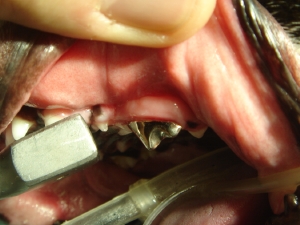

● 重 篤 な 破 折 に お い て フ ィ ル ピ ン を 用 い て 歯 を 再 建 し た 症 例

前述までと同様のP4の破折ですが、遠心根(より喉に近い部位)を激しく損傷し歯肉に埋まってしまった子です。飼い主様はなんとか歯を残したいという希望を持っていらっしゃったのでピンを立てて歯を再建いたしました。

*上記画像内に説明があるように本来は「白線のライン」まで歯があったと予想されます。

*青い部分は歯肉内であるためレーザーでカットしなければ天井(頬側面)が歯肉内で破損します。

*フィルピンとは何でしょうか? 例えば家を建てるときに平地の上にそのまま家を建てたら台風がきたら一発で吹き飛んでしまいます。家を立てる際は地面にボルトをたててそれを支柱として家を建てます。これと同じく残存している歯の部位にボルトを立てて歯の強度を高めます。

*まずは大雑把にレジンをフローとペーストで固めていきます。続いてクラウンを作るための支台を構築しますが、場所や形が非常に不明瞭であるため、逆サイド(健康歯)を見ながら左右を反転させたコピーを作るつもりで構築していきます。

*パラジウム(銀歯)を作成し、二回目の沈静をかけて接着します。十分な強度を有しています。